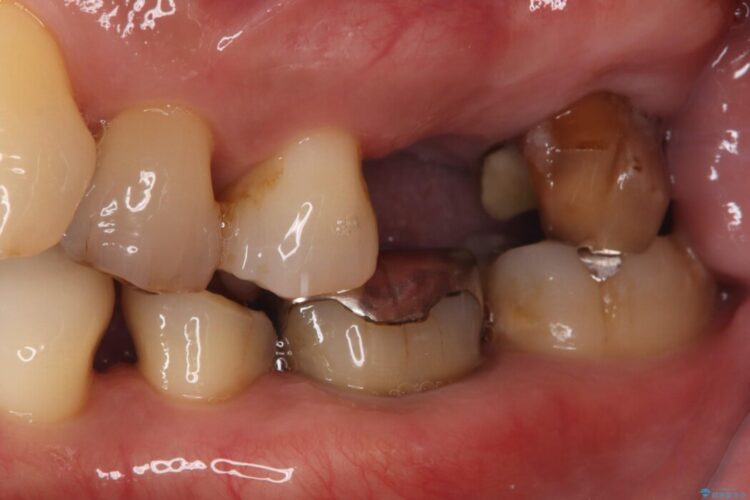

7番については抜歯と同時にインプラントを埋入する「抜歯即時埋入法」を選択。通院回数と治療期間を大幅にカットすることで患者様の負担を減らします。

あわせて6番目にもインプラントを行い、奥歯でしっかり力強く噛める状態を整える計画です。